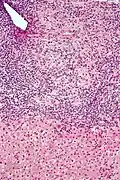

Mikrofoto einer primär biliären Zirrhose (HE-Färbung, niedrige Vergrößerung).

Mikrofoto einer primär biliären Zirrhose (HE-Färbung, niedrige Vergrößerung).